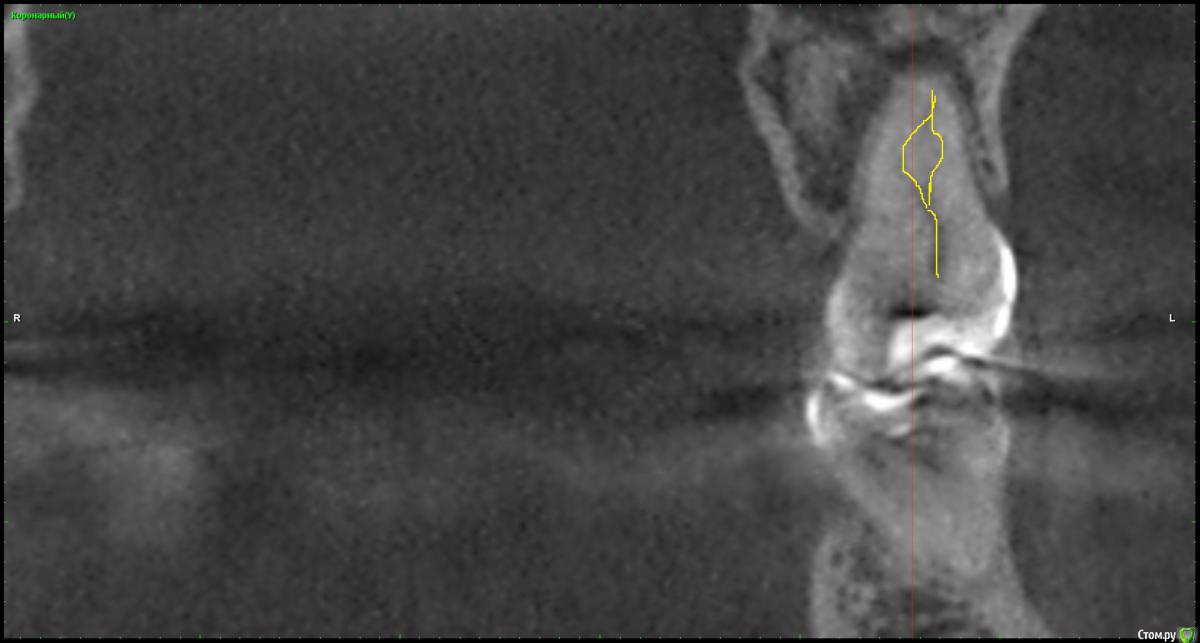

tatsiana.ma Опубликовано 23 ноября, 2016 Автор Поделиться Опубликовано 23 ноября, 2016 (изменено) 17-го числа без анастезии убирали метапекс. Два канала нормально, а в мезиально-щечном канале при прохождении файлами последней трети длины канала - возникает резкая боль, обильное слюноотделение. Боль не в самой верхушке, а когда до апекса остается еще несколько мм. И прохождение этих нескольких мм - пытка. Заложили апексдент.Вечером и по ночам зуб перестал ныть, по днем небольшая ноющая и иногда распирающая боль присутствует. В первые два дня после закладки апексдента отечность на щеке частично спала, но потом процесс остановился. Что может давать такую резкую боль?На КТ как раз над мезиально-щечным корнем есть странная вещь, см. фото. То ли такое разрежение костной ткани под кортикальной пластиной (стоматолог), то ли уплотнение самой кортикальной пластины в этом участке (рентгенолог). Ваше мнение что это над МЩК? это может быть связано с болевыми ощущениями при прохождении мщ канала? Изменено 23 ноября, 2016 пользователем tatsiana.ma Ссылка на комментарий

DmitrySH Опубликовано 30 ноября, 2016 Поделиться Опубликовано 30 ноября, 2016 http://s020.radikal.ru/i716/1611/5d/da2a5947af14.jpg с первого диска, все хорошо видно. 1 канал в переднем корне, в середине делится на 2, у апекса сходятся. как-то так 2 Ссылка на комментарий

DmitrySH Опубликовано 30 ноября, 2016 Поделиться Опубликовано 30 ноября, 2016 Сложная анатомия для лечения, что тут сказать 1 Ссылка на комментарий

tatsiana.ma Опубликовано 1 декабря, 2016 Автор Поделиться Опубликовано 1 декабря, 2016 Сложная анатомия для лечения, что тут сказать Спасибо за помощь!Подскажите, на практике (не в теории) реально пройти и почистить такую загогулину? и чем-то запломбировать? с трудом представляю как можно туда напаковать гуттаперчевые штифты И если я правильно поняла из вашего изображения как проходят каналы... и как мне изначально полгода назад "пропилили канал" под пломбирование, то создается впечатление, что эндомотором прошли между реальными каналами, отсюда и отек, и боли в мщк, когда файлом задевают участки выхода нерва Ссылка на комментарий